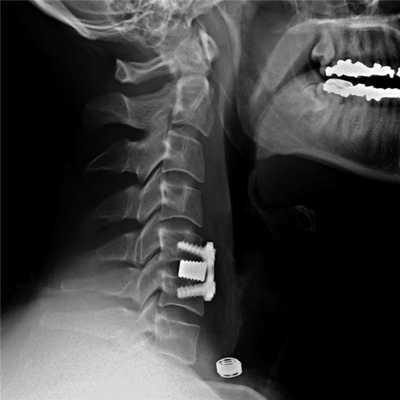

Импланты шейного отдела позвоночника на рентгене.

Представлены КТ пациента до и после оперативного лечения по поводу осложненного перелома пятого шейного позвонка. Выполнена корпорэктомия пятого шейного позвонка с комбинированным корпородезом аутокостью из подвздошного гребня и пластиной китайского производства.